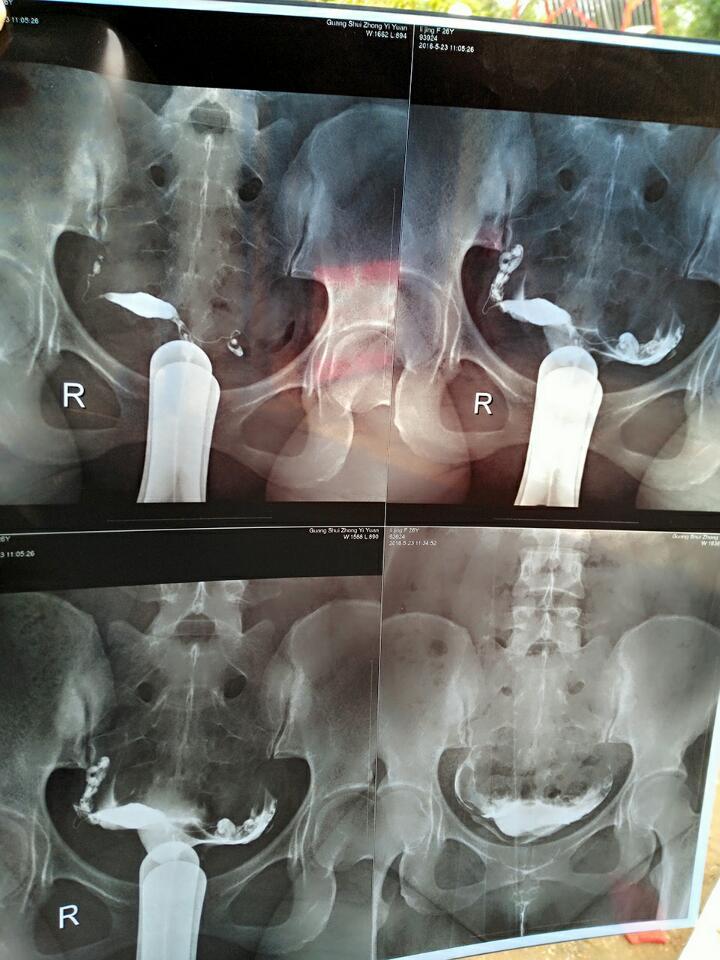

想生小孩,这是我做造影的片子,医生说输卵管积水,输卵管炎,请问这个要怎么治? 想生小孩,这是我做造影的片子,医生说输卵管积水,输卵管炎,请问这个要怎么治? 点击展开 189*****620_zv2Y 2016-05-26 10:39 为您推荐: 其他回答 听医生的! 无语_VVFQ 2016-05-26 12:08 嗯。是呀。治病这中医也不能保证,除非江湖郎中 zh307707096 2016-05-26 11:37 中医可以考虑。效果没人能预测 zh307707096 2016-05-26 11:26 但是毕竟是手术创伤大 zh307707096 2016-05-26 11:17 可能怀孕快 zh307707096 2016-05-26 11:17 加载更多 相关问题 输卵管积水的主要原因是慢性输卵管炎引起的吗?可是我怎么一点感觉都没有,要不是去做妇科检查,我还、、 本人想打算要生小孩了急急,输卵管有积水右侧,右侧见34;19输卵管回声左侧见28;11液性暗区且增粗10mm 子宫输卵管炎并积水怎么办、每月月经正常、现在月经刚来、要在月经干净三天后去打消炎针吗